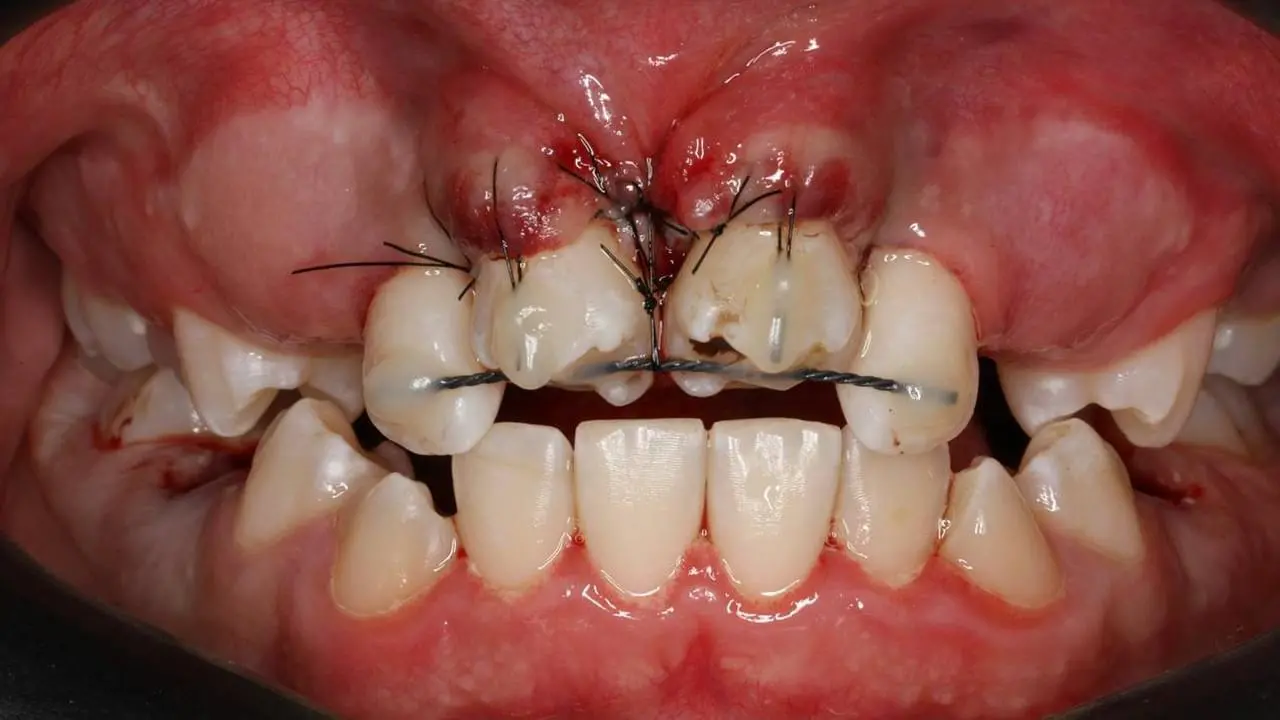

Коли лікар-стоматолог стикається з травмою постійного зуба у дитини, часто необхідно мобілізувати максимум знань і навиків: від реставрації до хірургії. Але найперше - це правильно визначити тактику. Наш курс допоможе відповідним чином приймати рішення в різних клінічних випадках травми постійних зубів у дітей. І не тільки приймати рішення, а і належно їх реалізувати в лікувальну тактику. На детальних клінічних прикладах ми демонструємо належну клінічну тактику та техніки, які часто допомагають врятувати постійні зуби юних пацієнтів.